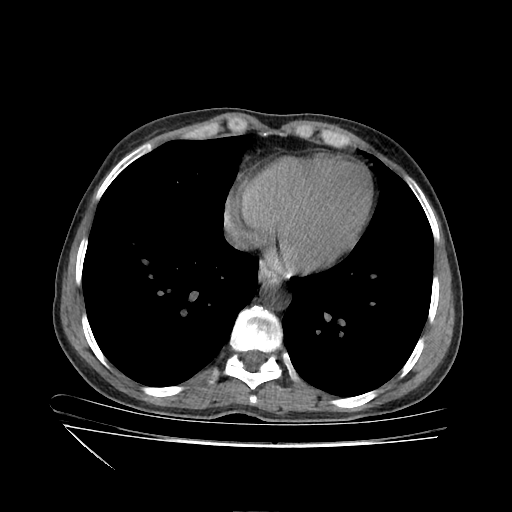

Generated VENOUS CT scan (A→B translation)

Full window (WL 1023.5, WW 4095 β†’ Low βˆ’1024, High +3071)

Actual HU range: [-1024.0, 959.4]